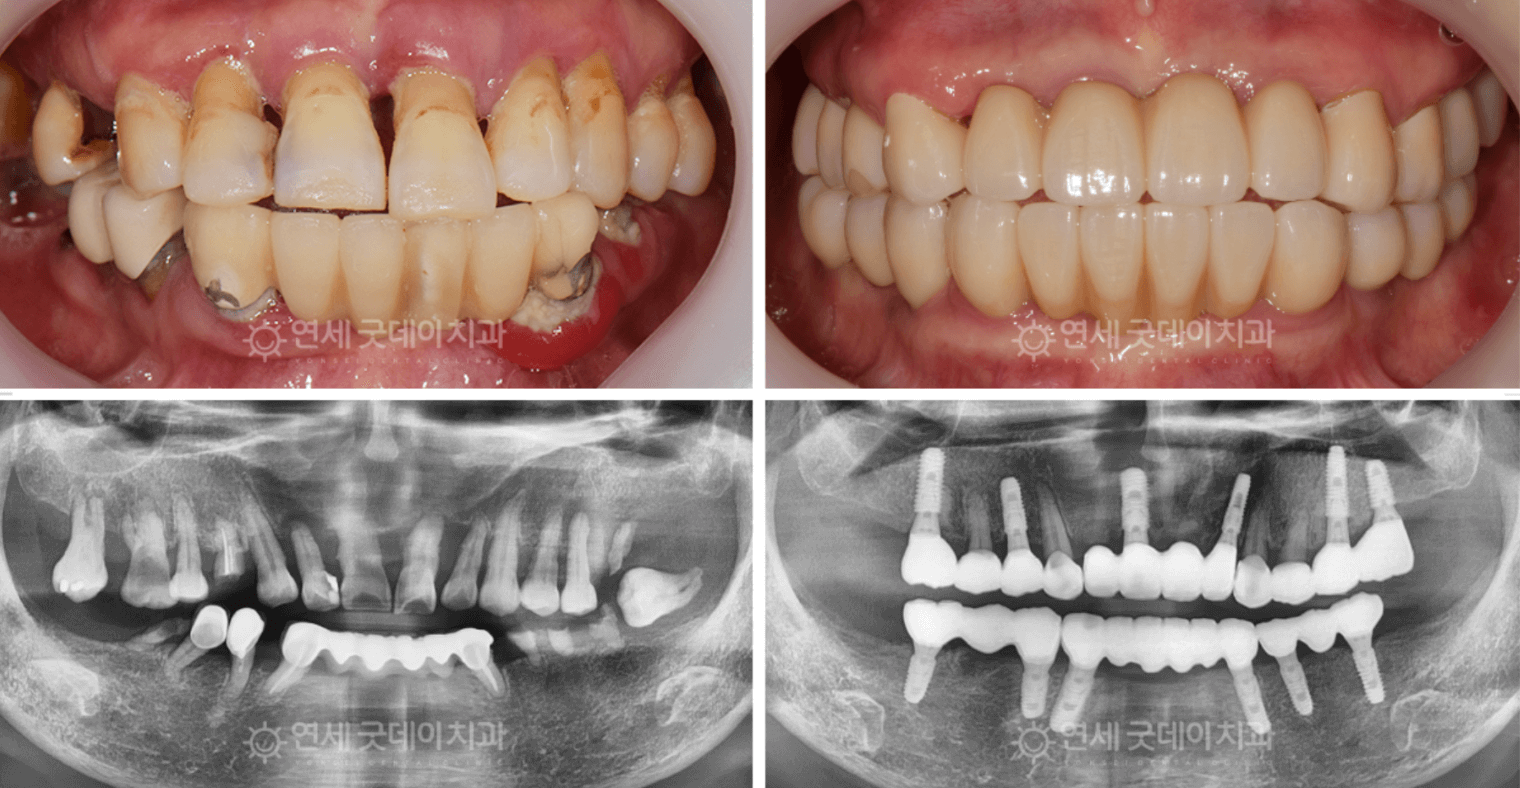

缺牙可能會影響您的自信、口腔健康以及整體生活品質。位於首爾江南的延世GOOD DAY牙科診所,提供先進的牙科植體,作為替代缺失或受損牙齒的長期解決方案。我們經驗豐富的植牙專科醫師,運用最新科技,為您打造自然、美觀、耐用且功能完善的牙齒修復,量身訂製符合您的需求。

20多年臨床經驗保障長期成功 —— 注重堅固的骨支撐與穩定的牙齦基礎

植牙不僅需要高品質的材料,更需要臨床經驗豐富的醫師,才能確保效果持久,維持20年以上。

在延世Good Day牙科診所,我們直接採用大學醫院等級的手術流程。

即使是八、九十歲的高齡患者,或是患有高血壓、糖尿病、骨質疏鬆、骨量不足等以往被告知無法植牙的情況,也在我們這裡獲得了卓越的治療效果。

透過全面考量患者健康狀況的個人化方案,我們自豪地呈現 延世Good Day的5大核心植牙技術,為您帶來卓越且長期穩定的成果。